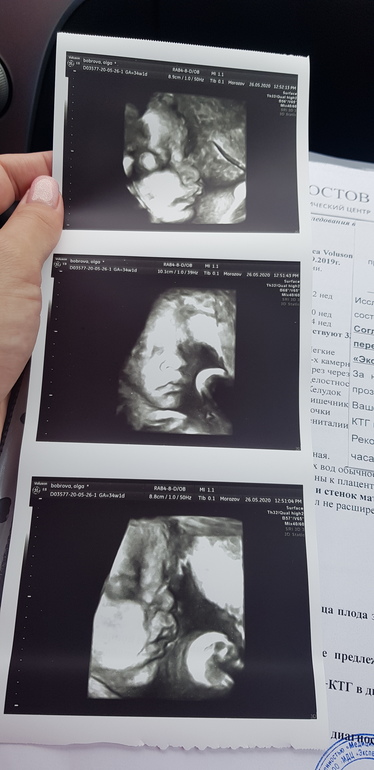

Узи в 34 недели❤

Я думаю так и должно быть узи. А то мы нервничает, а это вредно. И ещё раз убеждаюсь что в по фото видно на кого похож. Наша будет курносая как мама:)

Спасибо😊 я вообще шла на обычное узи, а в процессе мне доктор решил в 3Д показать. Это клиника Эксперт на Зорге

Сама не ожидала, что столько впечатлений будет от 3Д изображения😊 Хороший мне кажется вес у Вас, средний

Спасибо🤗 особенно приятно, т.к. и не ожидала увидеть. На 3 скрининге вообще мне личико не показывали

Тут еще как повезет🙂 У нас на 2 скрининге доча повернулась попой и ни в какую развернуться не хотела. В три захода делали узи, чтобы все измерить